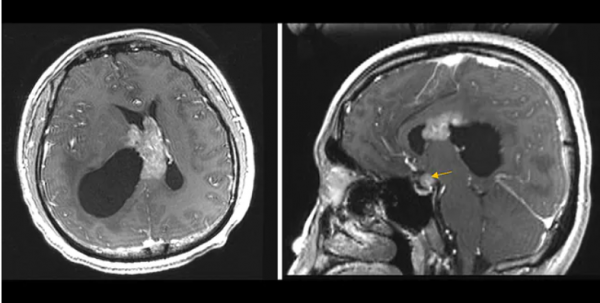

病例1

患者男,26歲,因意識模糊進行性加重、激越、感覺中樞減弱3周就診。影像學顯示沿透明隔的增強腫塊,延伸至側腦室的內側從而引起梗阻性腦積水,伴右側腦室顳角陷閉。右側矢狀面影象顯示鞍上間隙伴隨增強病變(黃色箭頭)。

腦室周圍區域和鞍上空間的串聯病變表明中樞神經系統(CNS)生殖細胞瘤,但其他病理,如神經膠質瘤和CNS淋巴瘤,則存在差異。CNS生殖細胞瘤約佔所有兒科腫瘤的3%。雖然大多數是在兒童時期被診斷出來的,但有些可能是在以後被發現,例如該患者。